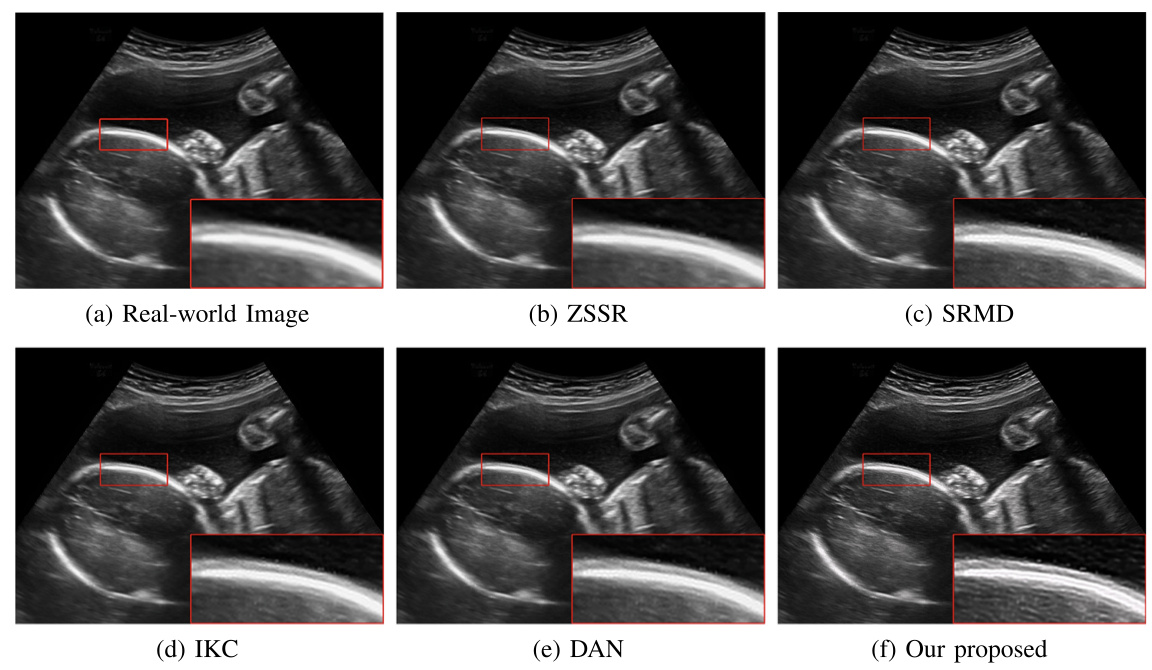

对于超声临床诊断而言,超声影像超分辨(ultrasound image super-resolution)可以提高超声成像质量,从而提高疾病诊断的准确性。但由于传感设备和传输介质的差异,实际场景中超声成像其退化模糊过程是未知且不可控的。为了解决未知退化场景超声医学影像准确超分辨的难题,团队提出了一种有效的基于退化模糊自估计且结合渐进残差学习和记忆提升机制的超声影像盲超分方法,初步实现了真实场景超声影像准确超分辨。相关研究成果发表在人工智能、计算机医学信息交叉领域一区TOP期刊《IEEE Journal of Biomedical and Health Informatics》(IF: 7.7)。公司为论文第一完成单位,必一运动刘恒教授、硕士生刘建勇分别为论文第一、第二作者。

(真实场景超声影像盲超分效果对比图)